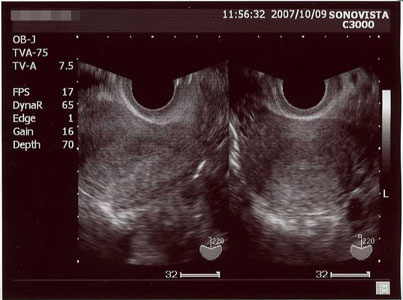

平日に仕事がお休み出来るのが、火曜日だけなため、10月9日(火)に産婦人科へ。

そこでの尿検査も「陽性」だったので、エコー撮影。

↓

折角撮ったのに、なーんにも写らなかった(;´・ω・)

まだ来院が早すぎたのかな?

でも陽性は陽性なので、また一週間後に再度検診です。

出産予定日も「?」マークw